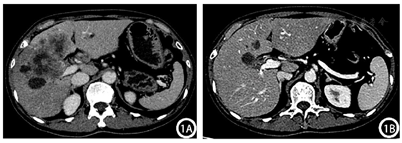

腹部增强CT:肝脏大小、形态正常,肝左内叶及肝右叶见大片状稍低密度影,增强扫描呈边缘强化,中心未见明显强化,邻近胆管扩张,门静脉右支受累,肝门区见多发肿大淋巴结,增强后强化不均匀;胆囊不大,囊内未见异常密度及异常强化灶。考虑胆管细胞癌可能,并肝门淋巴结转移(图1A)。腹部增强MRI:肝左内叶及肝右叶胆管扩张呈囊状异常信号灶,管壁增厚,其内及周围肝实质见多发片状T1WI低/稍低信号,T2WI高/稍高信号,DWI边缘呈明显高信号,中央稍高信号,增强扫描胆管及肝实质病灶呈环形强化,中央囊液不强化;胆囊底壁近肝实质处不规则增厚,DWI呈局部高信号,增强扫描轻度强化;门静脉右支受累,肝门区见多发肿大淋巴结,较大者大小约为2.0 cm×1.0 cm,形态不规则,增强后强化不均匀;胰头区见片状异常信号灶,DWI明显高信号,胰管未见明显扩张。考虑肝左内叶及肝右叶占位,胆管细胞癌可能,并肝内扩散、肝门淋巴结转移,胆囊底、胰头区、门静脉右支受侵可能(图2A)。

结合患者肿瘤分期,分别于2022年1月5日、2022年2月14日、2022年3月16日进行了3个周期的转化治疗,方案为吉西他滨+替吉奥+仑伐替尼+卡瑞利珠单抗:吉西他滨1.4 g静脉滴注、替吉奥50 mg每日2次(服用4周停2周)、仑伐替尼8 mg口服每日1次、卡瑞利珠单抗200 mg。患者规律经以上治疗后,于2022年4月11日返院,行腹部增强CT:对比前片:肝脏占位病变范围较前稍缩小、强化程度大致同前,肝门区肿大淋巴结本次扫描未见显示(图1B)。腹部增强MRI:对比前片,肝左内叶及肝右叶占位较前明显缩小,肝门部肿大淋巴结未见显示,胆囊底部结节状异常信号灶范围较前缩小,胰头区受累病变DWI未见高信号,门静脉右支及右侧肝内胆管受累同前(图2B)。结合影像学检查,患者ICC分期:T2N0M0(Ⅱ期),转化治疗成功,达到降期目标,遂完善术前准备后,于2022年4月20日在全身麻醉下行"右半肝切除+胆囊切除+腹腔淋巴结清扫(第8组3枚、第12组3枚、第14组4枚)+胆肠吻合+腹腔冲洗置管引流",手术顺利,术后恢复良好。术后自2022年6月9日开始,患者定期每3周返院接受全身化疗及免疫、靶向治疗,方案:吉西他滨1.4 g每3周1次+培他滨1.75 g每日2次(治疗2周停药1周)+仑伐替尼8 mg口服每日1次+卡瑞利珠单抗200 mg每3周1次;经3个周期治疗后,患者CA19-9无明显下降,遂改换方案:吉西他滨1.4 g每3周1次+卡培他滨1.75 g每日2次(治疗2周停药1周)+顺铂40 mg每日1次(连用3 d)每3周1次,以此方案治疗至今。